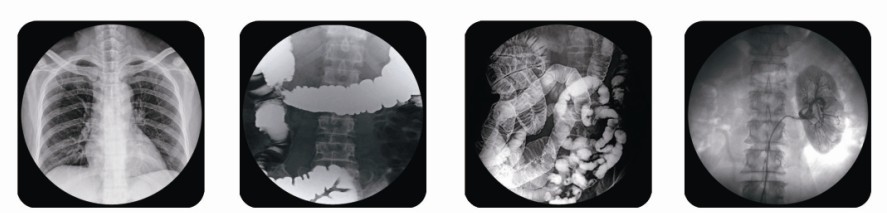

腸胃造影x光機其實也就是胃腸機,雖然該設(shè)備叫腸胃造影x光機但它功能還有很多,比如:可用于消化道造影、膽道造影、泌尿道造影以及下肢靜脈造影檢查患者身體各部位攝影、透視及其它創(chuàng)傷性常規(guī)檢查,可透視下進行骨折整復(fù)、取異物等工作。功能很全面,是醫(yī)療單位的首選設(shè)備。

目前,普朗公司推出的腸胃造影x光機9款可供用戶們選擇,下面為您展示的其中一款,點擊圖片下方紅色產(chǎn)品名稱可查看該產(chǎn)品的詳細介紹,另外您還可以通過電話聯(lián)系我公司客服了解普朗酶標(biāo)儀、洗板機、病人監(jiān)護儀、c型臂、小兒呼吸機等產(chǎn)品信息。

(普朗醫(yī)療——高頻醫(yī)用診斷X射線機PLD5800腸胃造影x光機))